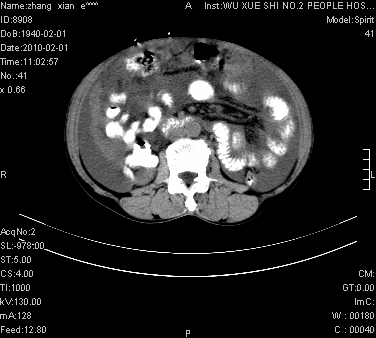

标题: CT24434:70岁 女 腹胀,腹水原因待查 [打印本页]

标题: CT24434:70岁 女 腹胀,腹水原因待查

大量腹水,脾脏囊性占位,子宫颈占位,右侧腹股沟淋巴结肿大,建议+c,先查妇科。

腹盆腔大量积液,子宫增大,子宫颈增大外形不规则,内见低密度影,膀胱后壁显示不清,右腹股沟肿大淋巴结,脾脏囊性占位,子宫颈占位,子宫颈癌?建议增强。

考虑:1、腹膜转移,大量腹水;

2、脾占位性病变;

3、左侧卵巢占位性病变,建议增强进一步检查。